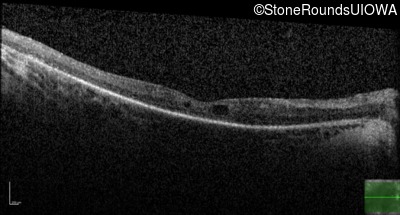

Optical Coherence Tomography - Left - 20/70 +1

Exemplar / OCT Stack